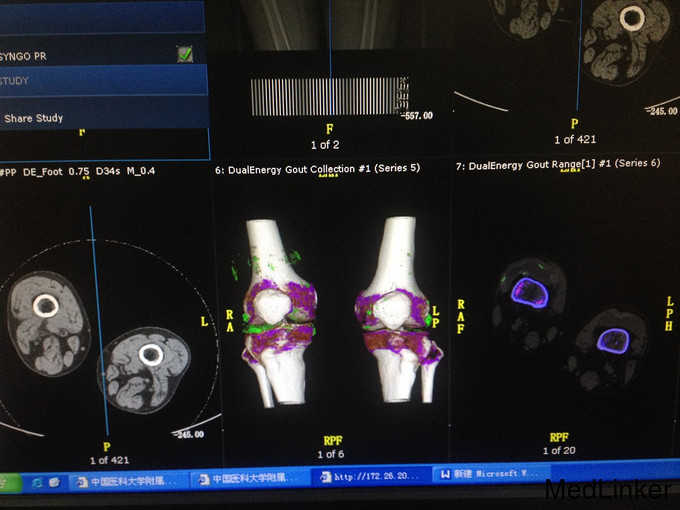

入院查体:左足趾指、双肘关节,胫骨前部可见多处痛风结节,有轻微触痛,双肘关节及膝关节活动轻度受限。 辅助检查:血脂分析:HDL-C 0.98mmol/L、LDL-C 3.80mmol/L。血清尿酸测定:UA 517umol/L。ALP 170U/L、GGT 226U/L、TBIL49.7umol/L、CHE3694U/L,DBIL 14.7umol/L。尿微量蛋白(5项):a1-MG 24.40mg/l。7.骨代谢标志物(男):B-Crosslaps 829.80pg/ml、|Osteoc17.25ng/ml、PTH65.41pg/ml。HbA1C 6.30%。糖耐量试验、胰岛功能系列: (0分) (120分) GLU(mmol/L) 4.05 7.3 IRI(mIU/L) 7.08 27.35 CPS(pmol/L) 805.94 2370.33 肾上腺皮质激素系列: 8:00 15:00 24:00 ACTH 26.45pg/ml 11.16pg/ml 1.00pg/ml COR 235.60nmol/L 213.80nmol/L 453.50nmol/L 肾功能:Cr76umol/L。CRP 47.10mg/l。PCT 2.34ng/ml尿系列:胆红素+,尿胆原++,蛋白质+,红细胞数0-4/HP,双手DR:左手第一掌骨及指骨改变。双足关节DR:双足改变,符合痛风,请结合临床。 双侧膝关节DR:右侧胫骨髁间嵴骨质增生。肝胆脾胰、双肾、膀胱残余尿量彩超:轻度脂肪肝,双肾小结晶或结石,残尿量约66ml。心脏彩超:左室心肌厚度正常高值,主动脉瓣退行性变,静息状态下左室整体收缩功能正常。肺部CT平扫(64排):右肺上叶局限性气肿。右肺及右侧胸膜陈旧性病变。双侧腋窝淋巴结肿大。左侧肩关节DR正位:左侧肩关节退行性变。左膝关节痛风双能3D-CT扫描:双膝多发绿色伪彩,考虑尿酸盐结晶,请结合临床。双侧胫骨平台骨质改变。双侧关节腔及髌上囊积液。

讨论:痛风诊断的金标准为关节积液内或白细胞内发现有尿酸盐结晶,但临床使用受限,而双能量CT痛风结石识别功能是目前影像检查技术中唯一能显示出关节中可能存在的尿酸盐结晶的技术。此病例中,图中的绿色影即为典型的尿酸盐结晶。